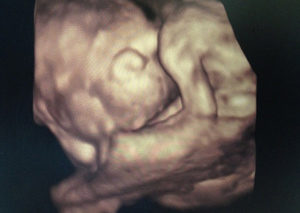

Ta nowa prezentacja (prezentacja 4D) pochodzi od dodania czwartego wymiaru jakim jest czas. Badanie płodu metodą 4D pozwala nie tylko na obrazowanie przestrzenne płodu ale również pozwala na obserwację ruchów twarzy, obserwację otwierania i zamykania oczu, ruchów języka, ssania palców. Przy korzystnym ułożeniu płodu, w odpowiednim wieku ciążowym ( najlepiej pomiędzy 15. a 35. tygodniem ciąży) możliwa jest diagnostyka szeregu wad rozwojowych płodu. Badanie 4D pozwala też na precyzyjne obrazowanie rozwoju płodu i umożliwia podejrzenie wyglądu dziecka, którego wygląd jest niemal identyczny z jego rzeczywistym wyglądem.

Zastosowanie techniki 3D i 4D ma szczególne zastosowanie w położnictwie. Umożliwiają precyzyjną ocenę narządów wewnętrznych płodu, np. serca, mózgowia, kręgosłupa, twarzy oraz w sposób istotny pozwalają na zwiększenie wykrywalności wad budowy płodu .